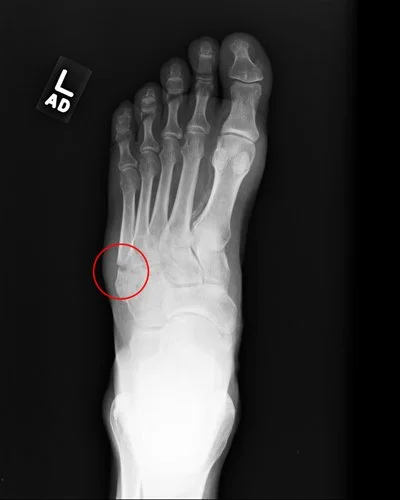

Along with the X-rays, I was given a report. "A transverse fracture of the fifth metatarsal." A small bone, but after doing some research online, I'm a little apprehensive about it. When the doctor who released me from the ER said I might need surgery, I really didn't pay much attention to her. But now I'm not so sure. We'll see. I finally have an appointment with an orthopedic foot specialist on Monday.

He put my foot on a lead dinner plate and zapped me with the hair dryer. The X-rays appeared on the computer screen instantly, all digital, nothing to be developed. "Yup," he said. "There it is." With each new angle, he pointed out the "significant amount of displacement" and said it needed to be reset and screwed in place with a cannulated titanium screw. "It doesn't make any sense to wait, it's not going to heal the way it is."

"No, seriously," I said, "I'm here for my foot. I broke my fifth metatarsal, and the doctor is going to put a screw down the middle of it."